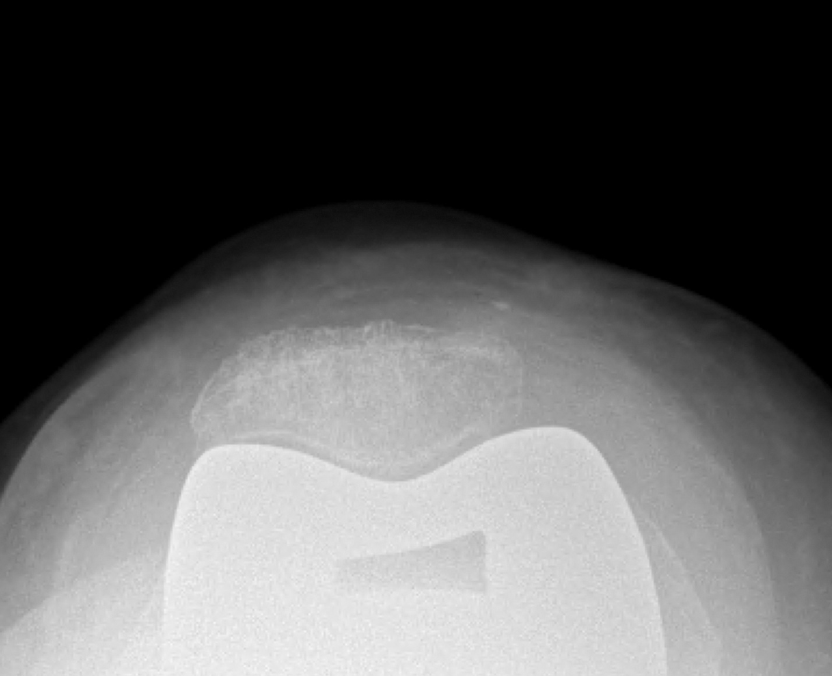

π Time for new frontiers in arthroplasty: advancing technology in execution and driving innovation in osseointegration. The challenge ahead is addressing the biological interface: filling the gap between bone and implant. By combining precision surgery with biologic and

Are you seeing more failures of the tibia or femur in modern cementless total knees? @PeltMD @jesslonner @nspiuzzi